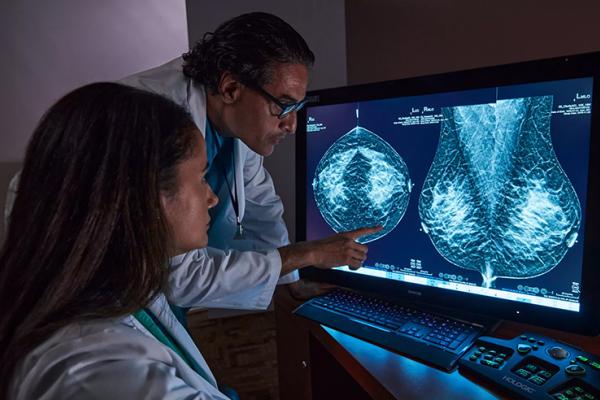

The Hologic range of biopsy site markers come in multiple shapes, gauges and lengths. The markers are compatible for use with x-ray, ultrasound and MRI guided biopsies. All markers come with an ergonomic and easy to use deployment device included.

Identify with Confidence

Research shows that the Tumark Professional X, Q and Vision biopsy site markers are accurate and easy to use.1